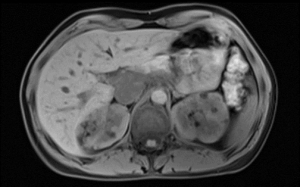

Abb. 5: MRT des Abdomens zeigt ein renalen Angiomyolipom links (orangener Pfeil) bei einer Patientin mit TSC-LAM (Abbildung mit freundlicher Genehmigung des Universitätsspital Basel)

Eine abdominale Beteiligung tritt insbesondere mit renalen Angiomyolipomen auf – gutartigen Tumoren, die ein hohes Blutungsrisiko bei >4 cm Grösse darstellen (Abbildung 5). Abdominale oder mediastinale Lymphangioleiomyome, Aszites und Lymphadenopathien können ebenfalls auftreten.